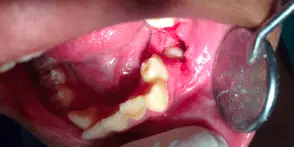

SURGICAL EXTRACTION OF IMPACTED PRIMARY MOLAR

A 8 year old boy reported to the department with a complaint of missing teeth in the lower left back teeth region. While recording the history his mother reported that the tooth in that region had not erupted. On clinical examination an edentulous space was seen and the first permanent molar had inclined towards this edentulous space. An OPG and IOPA were taken that showed the presence of an impacted primary second molar. Underlying it was a developing permanent 2nd molar. A surgery was performed for the removal of this impacted tooth which was followed by placement of a space regainer to distalize the permanent 1st molar.